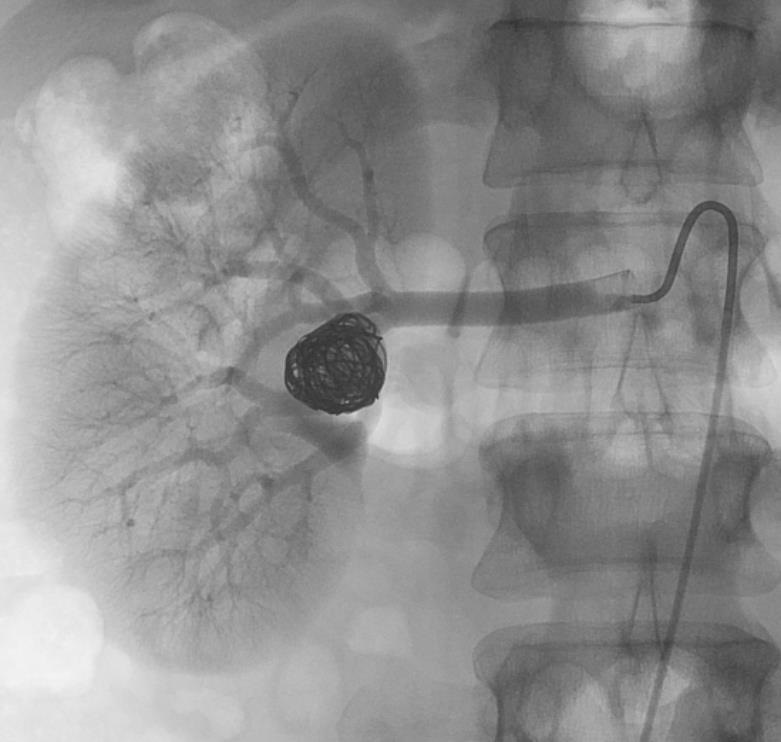

末端动脉阻塞(end-artery occlusion)

末端动脉栓塞:医源性肾损伤-移植肾活检

活检后动脉瘤破裂 |

微导管在载瘤动脉末端 |

载瘤动脉末端栓塞 |

Coil=3 |

直接动脉末端栓塞的过程是简单推出弹簧栓子(simply pushed out coil),但要求弹簧栓子的直径≥血管直径